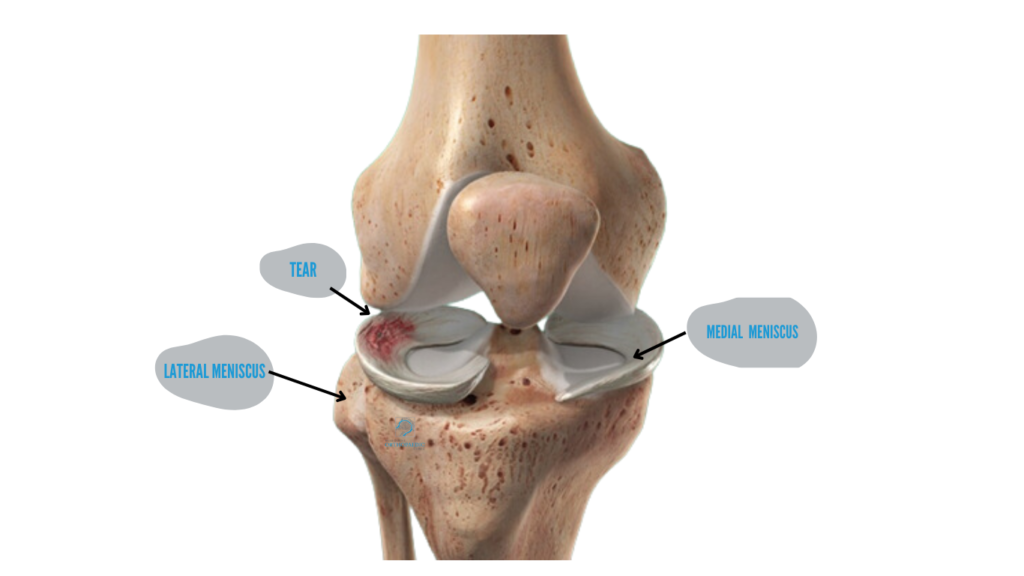

Meniscus surgery is a procedure aimed at treating damage to the meniscus, the crescent-shaped cartilage that acts as a shock absorber in the knee joint. Meniscal tears are a common injury, often caused by sudden movements, twisting, or degenerative changes due to ageing. The goal of meniscus surgery is to repair or remove the damaged tissue, helping restore knee function, reduce pain, and prevent further damage to the knee joint.

The meniscus is composed of two pieces of cartilage located in the knee joint, one on the inner (medial) side and one on the outer (lateral) side. A tear can occur as a result of acute injury, such as during sports, or through wear and tear over time. Meniscus tears are classified into different types based on the location and pattern of the tear, including: